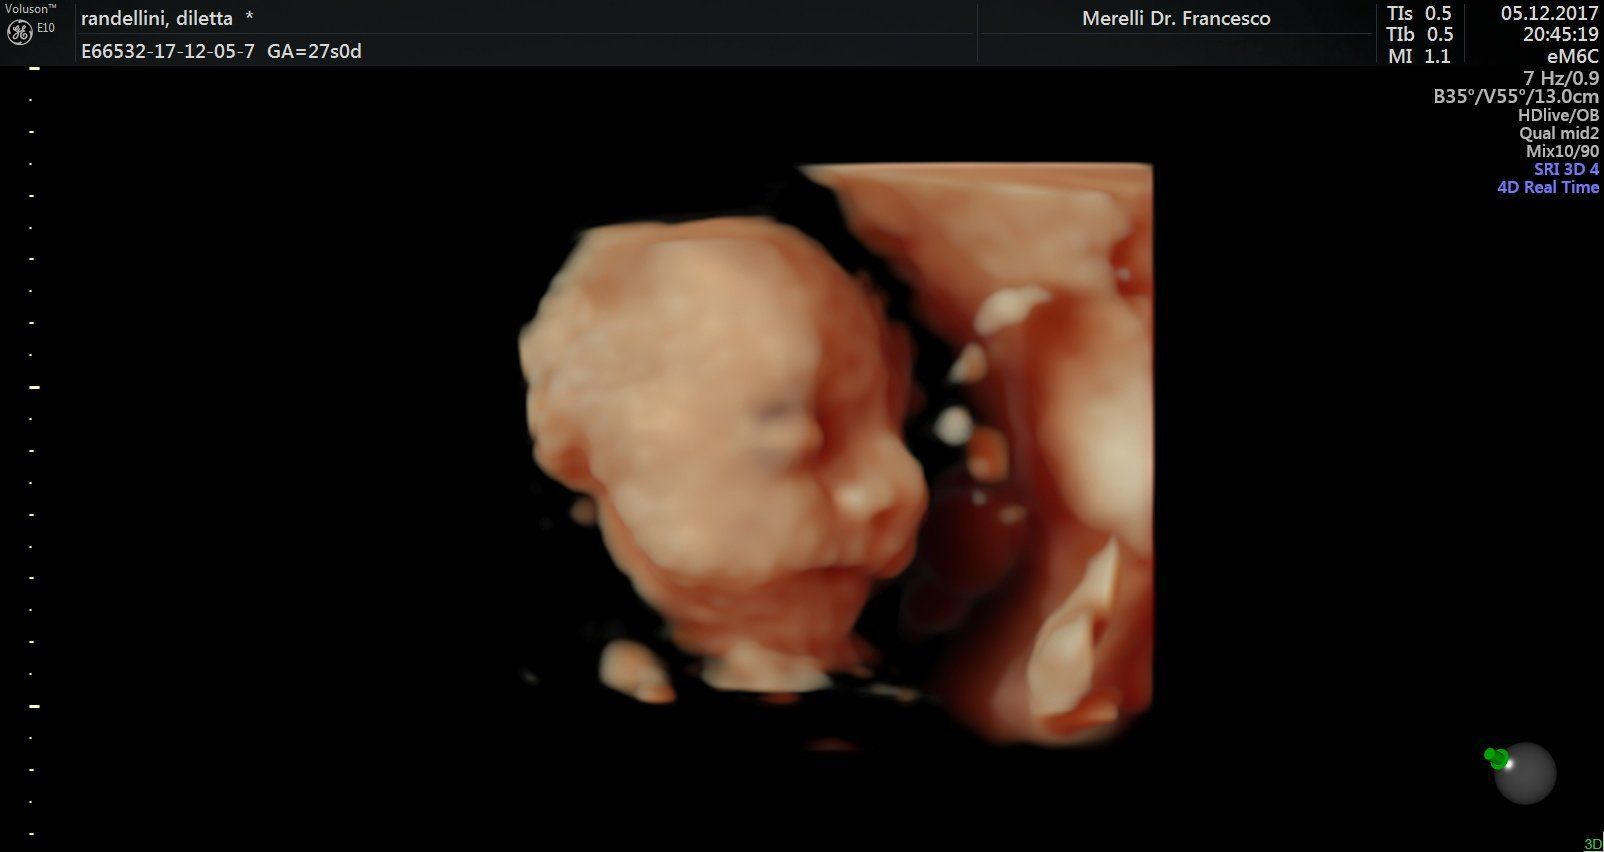

Il dr. Merelli esegue anche l'

ecografia ostetrica ginecologica tridimensionale.

- ecografie ostetrico - ginecologiche

- ecografia 4d